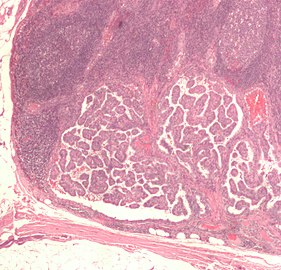

Lymph node with almost complete replacement by metastatic melanoma. The brown pigment is focal deposition of melanin